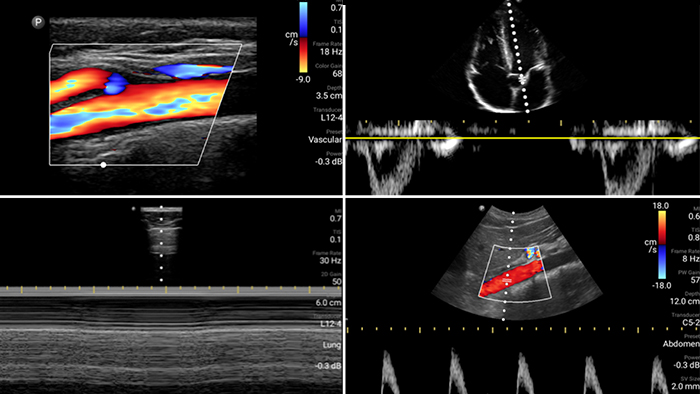

Lumify is with you

every step of the way

Evaluate, diagnose and treat your patients in

minutes with a multi-point POCUS exam.

Second case image

Broadband linear array transducer

Lumify L12-4 broadband linear array transducer

• 12 to 4 MHz extended operating frequency range

• Aperture size: 34mm

• 2D, steerable color Doppler, M-mode, advancedXRES and multivariate harmonic imaging, SonoCT

• High resolution imaging for shallow applications: soft tissue, vascular, superficial, musculoskeletal and lung

• Center line marker

• USB-C transducer with replaceable cable